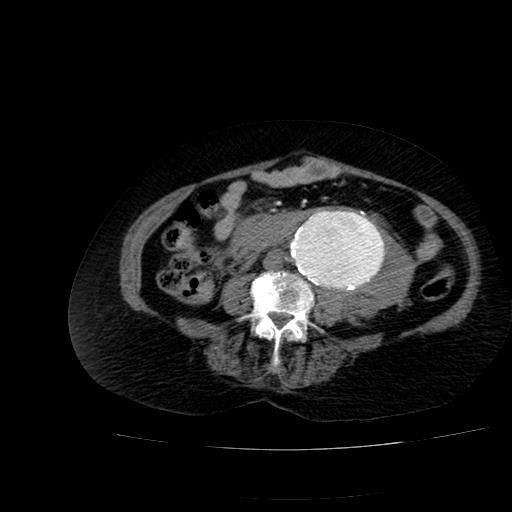

Endovascular aneurysm repair (EVAR) is an adequate means for treating infrarenal abdominal aortic aneurysms (AAA). However, secondary interventions are required in approximately 15% to 20% of patients. The aim of this paper was to report our knowledge with stent grafts in secondary interventions after EVAR in a 73-year-old patient. One of the exceptional complications of EVAR are endoleaks which may lead to expansion of aneurysm and rupture if not repaired.